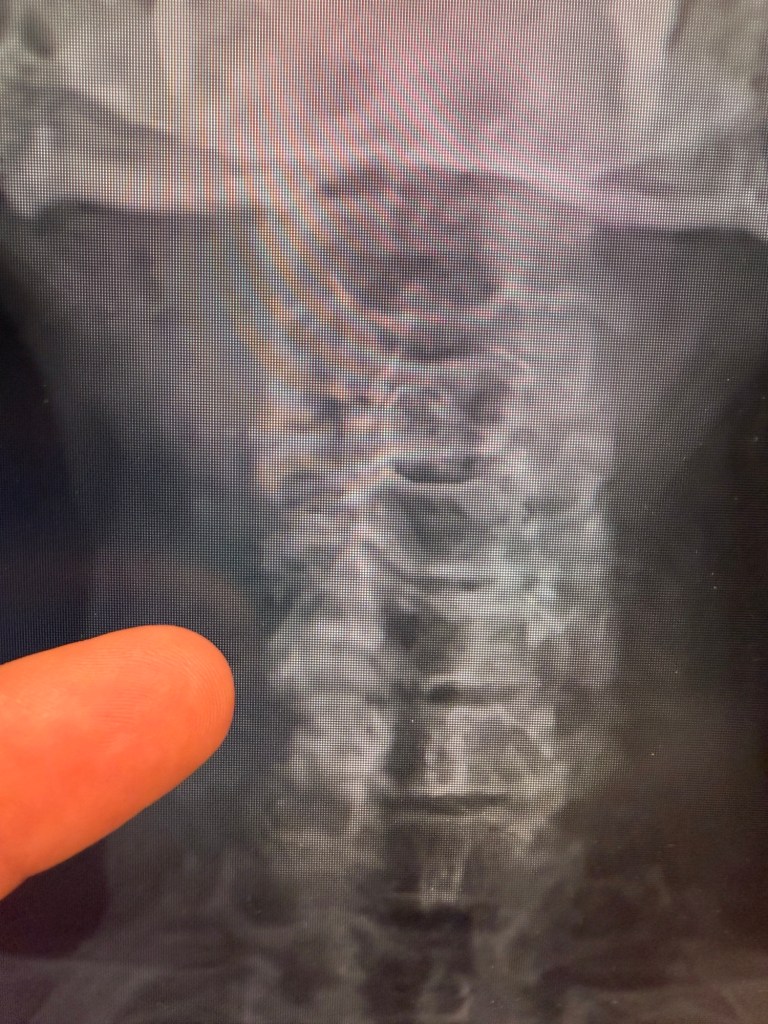

Finally saw my neurologist regarding herniated discs, and most notably, what to do about the nerve impingement at C5-6 that’s at the root of my numb/tingly finger on my right hand.

We talked about the varying treatment options and evaluated what makes the most sense. At the extreme end of the spectrum would be surgery and whether that means disc replacement or fusion. Fusion would be really bad as it means that I would have limited range of motion around my neck. Disc replacement is complicated and made more complicated by my age and the arthritis that is present. For now, this is a hard pass.